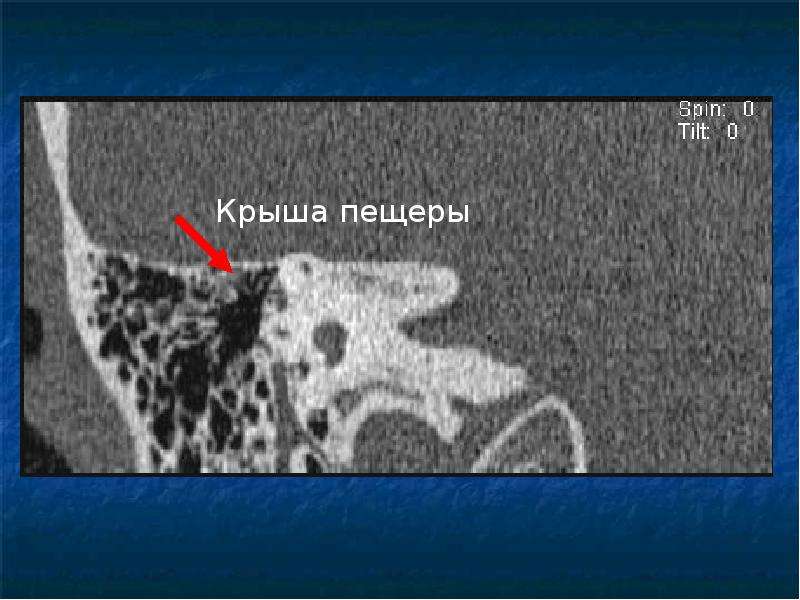

КТ анатомия сосцевидного отростка: особенности и показания